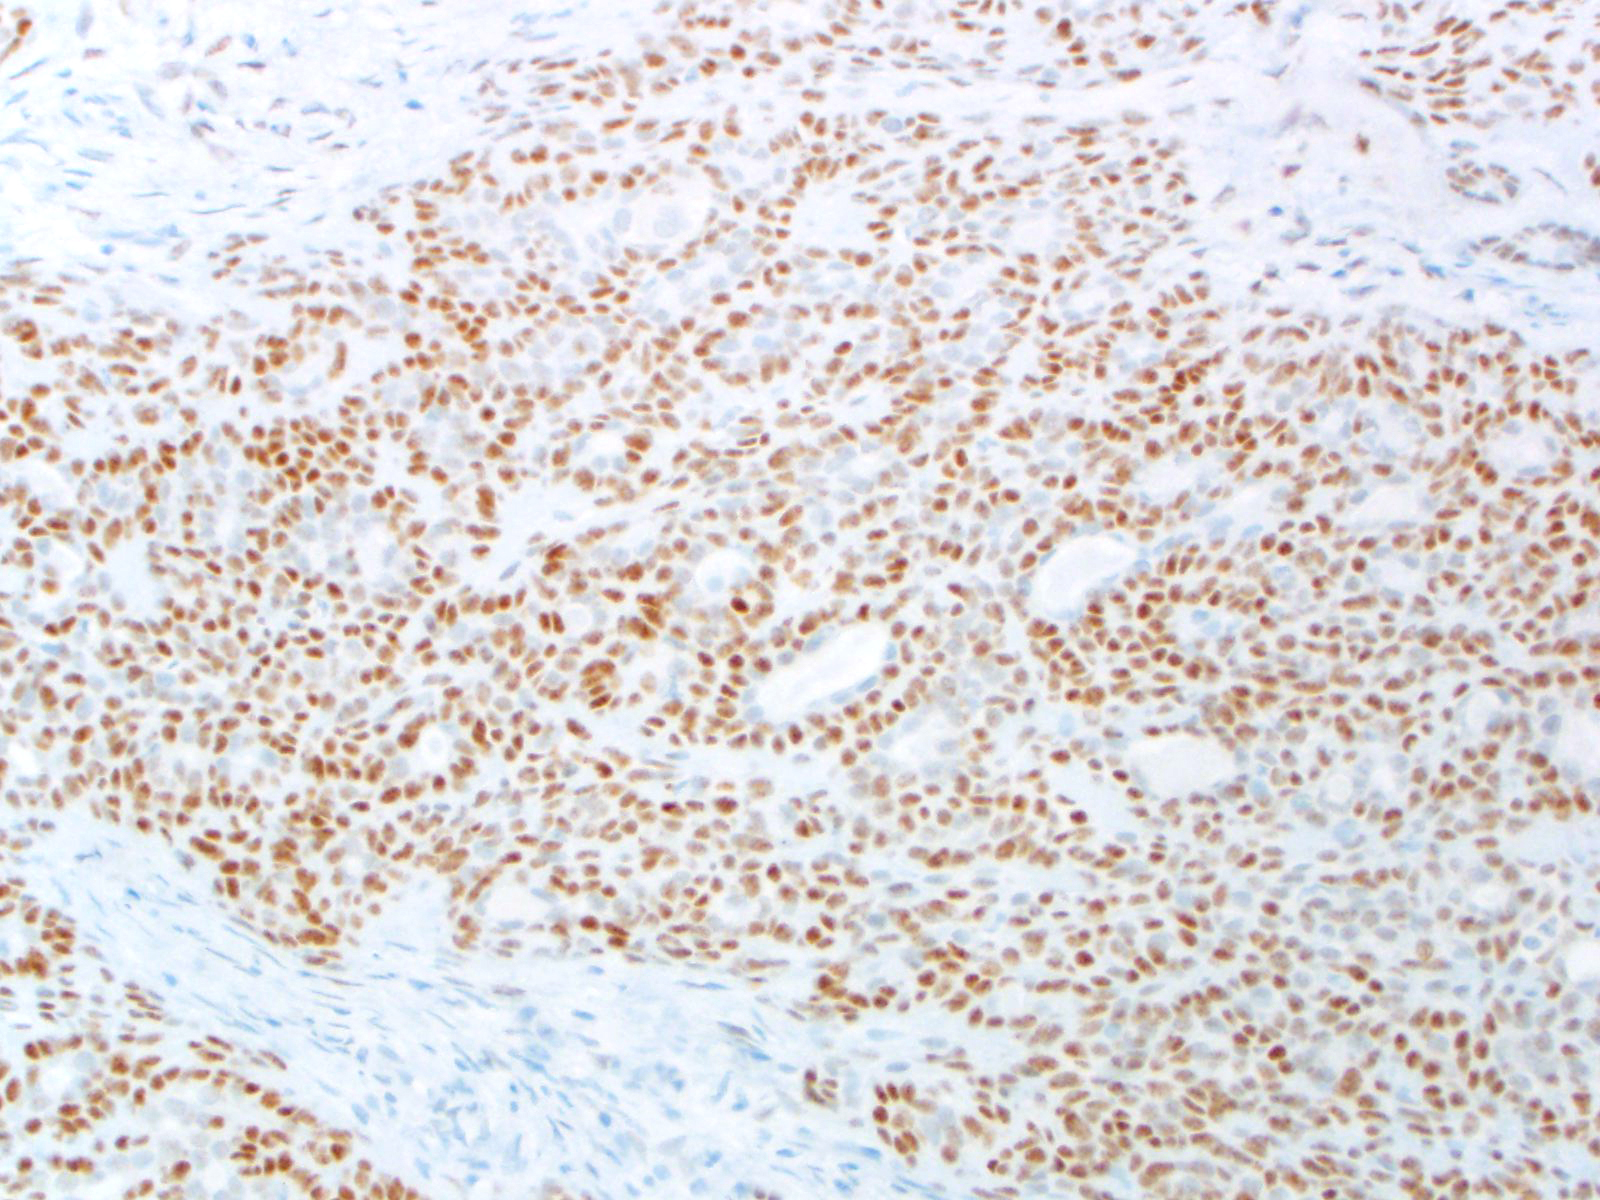

| 2SC |

S-(2-succino)-cysteine |

Rabbit polyclonal (Cambridge Research Biochemicals)

Hereditary leiomyomatosis and renal cell carcinoma (HLRCC) syndrome-associated RCC and leiomyoma

Most renal tumors and leiomyomas not associated with HLRCC

Staining Pattern

Cytoplasmic and nuclear

| HLRCC-associated leiomyoma |